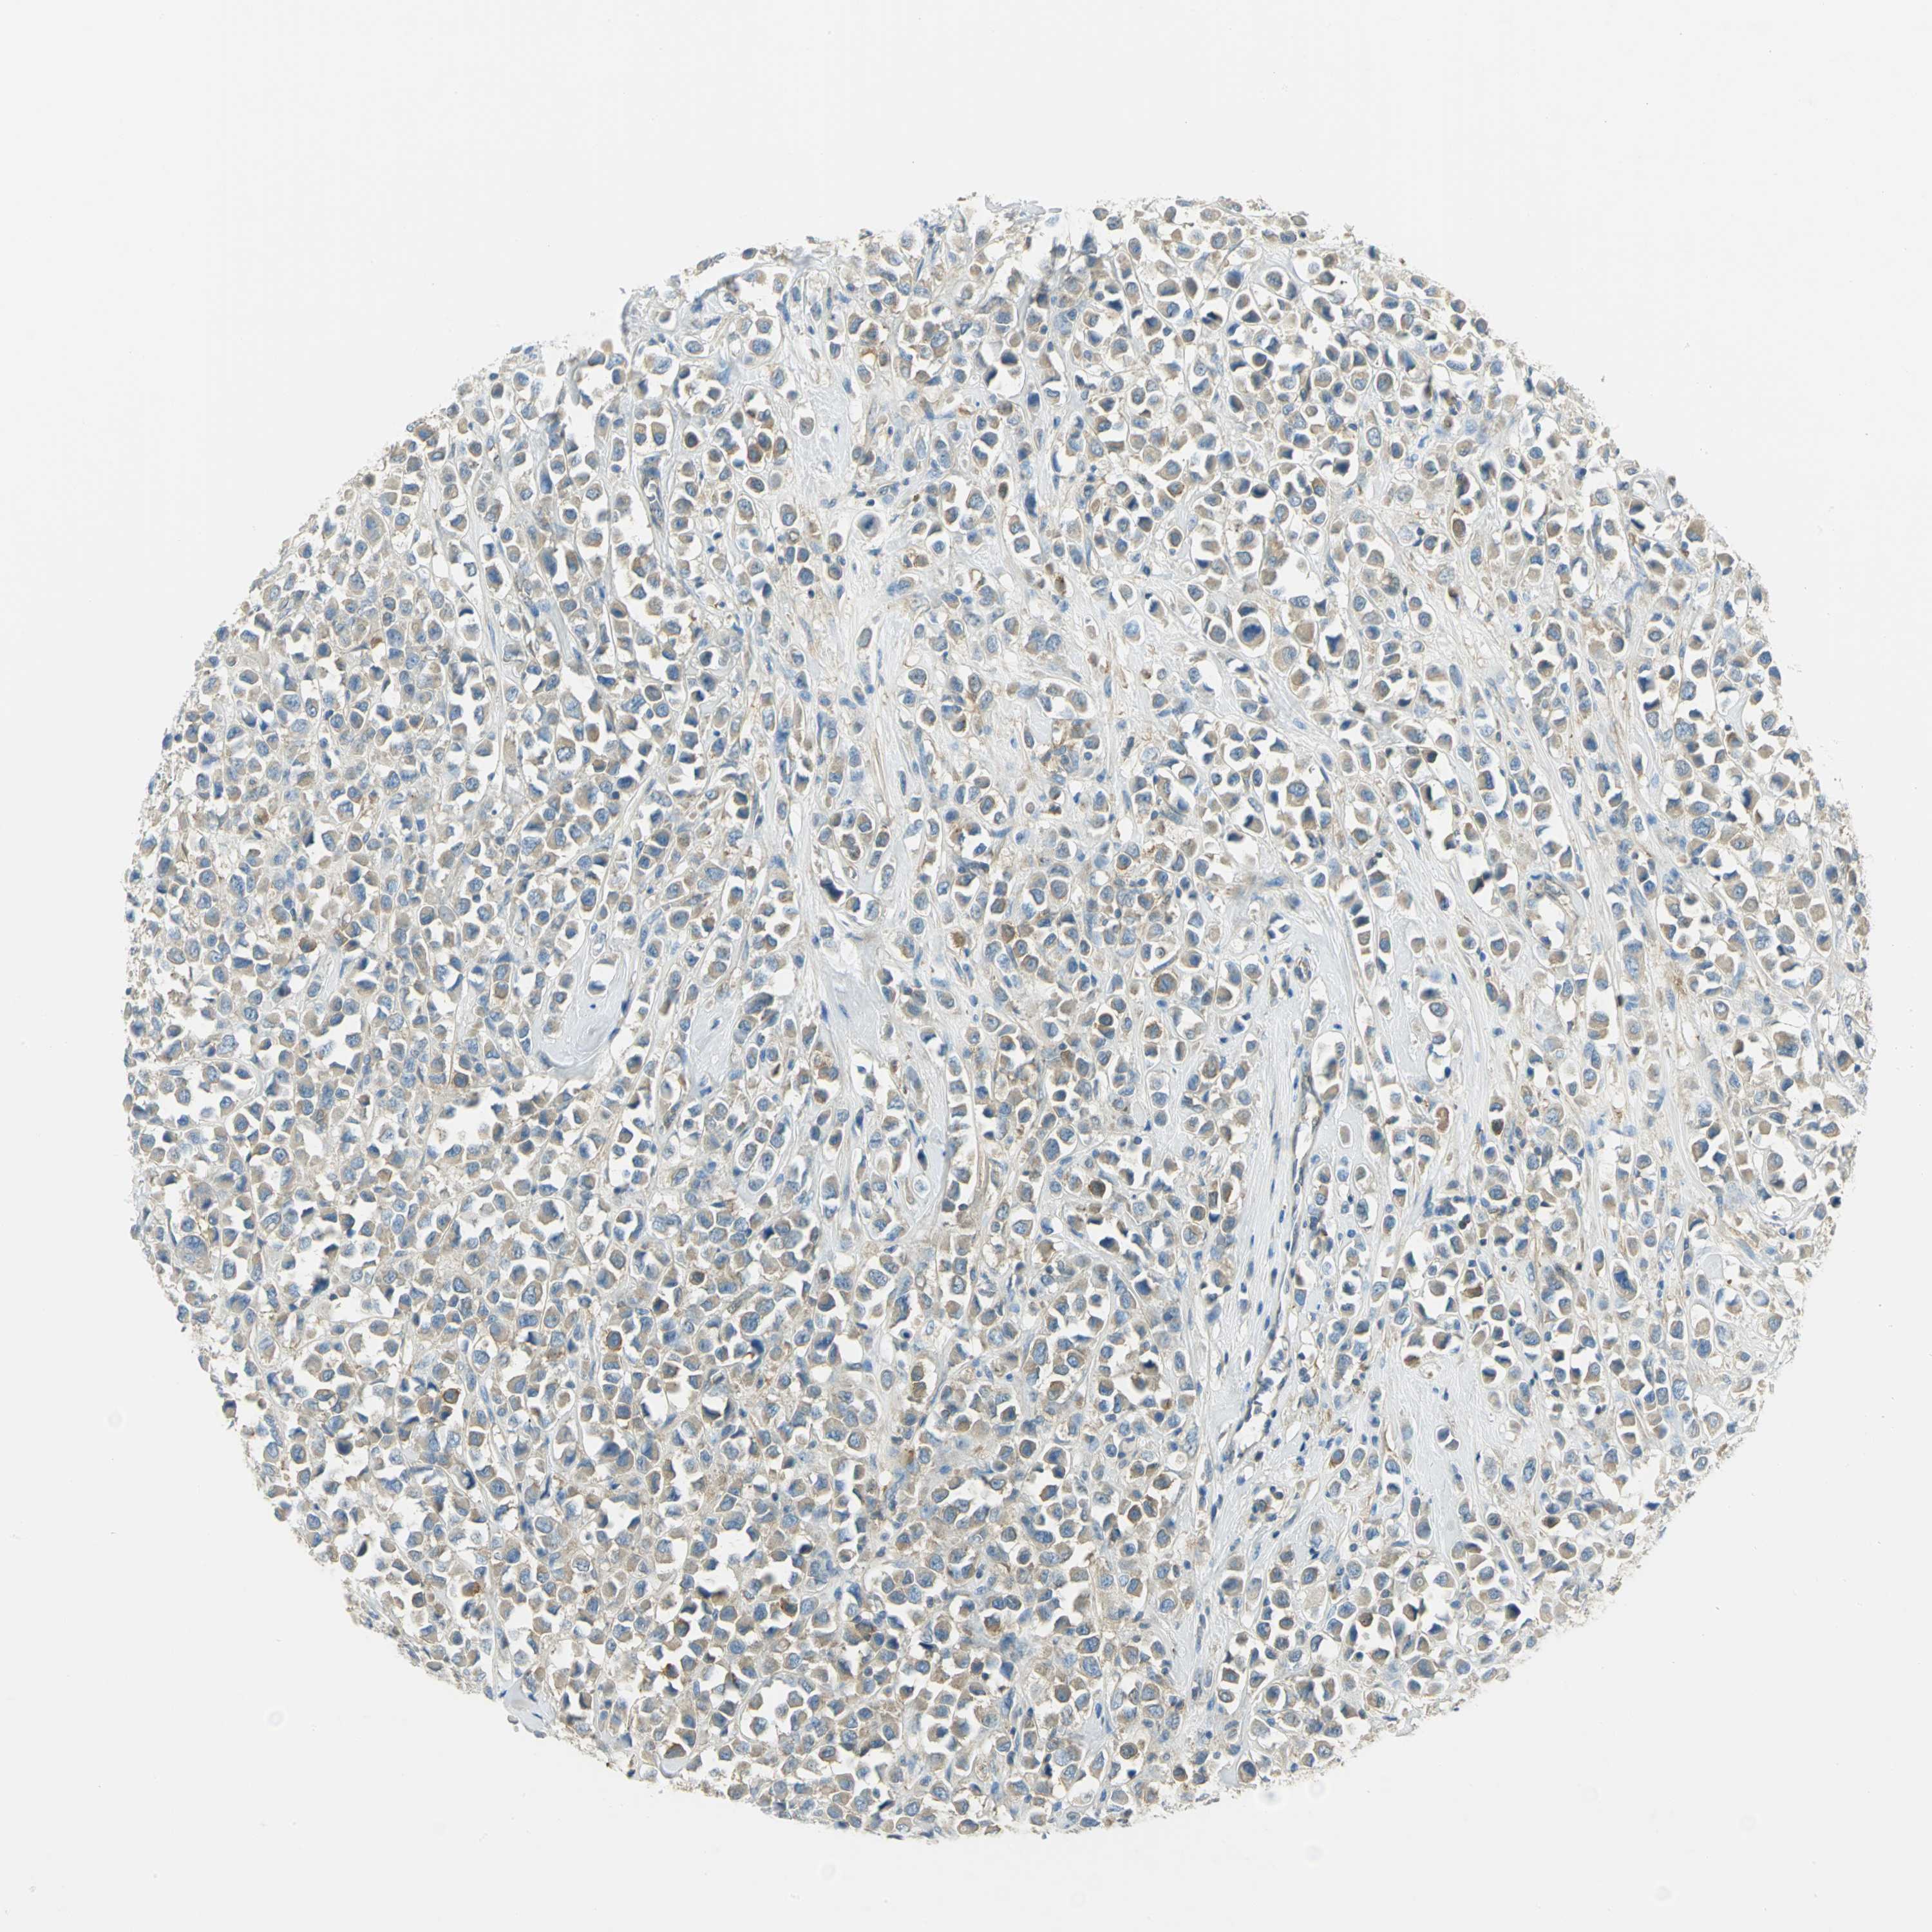

BRCA TCGA BRCA VALIDATION PROTEIN EXPRESSION

ANTIBODIES

AND

VALIDATION